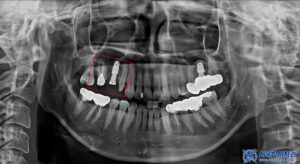

파노라마 촬영으로

전체 상태를 먼저 확인했습니다.

다만 크라운은 방사선 불투과성이 있어

내부 평가가 제한되므로,

정밀 엑스레이를 추가로 촬영해

보철물 하방 상태를 점검했습니다.

그 결과, 브릿지 아래쪽에

우식이 진행된 것이 확인되었습니다.

이에 신흥동치과 서울박사에서는

위쪽 브릿지를 모두 제거하고,

지대치는 크라운으로 다시 보철하며

인공치가 있던 부위는

임플란트 식립을 진행하기로 했습니다.